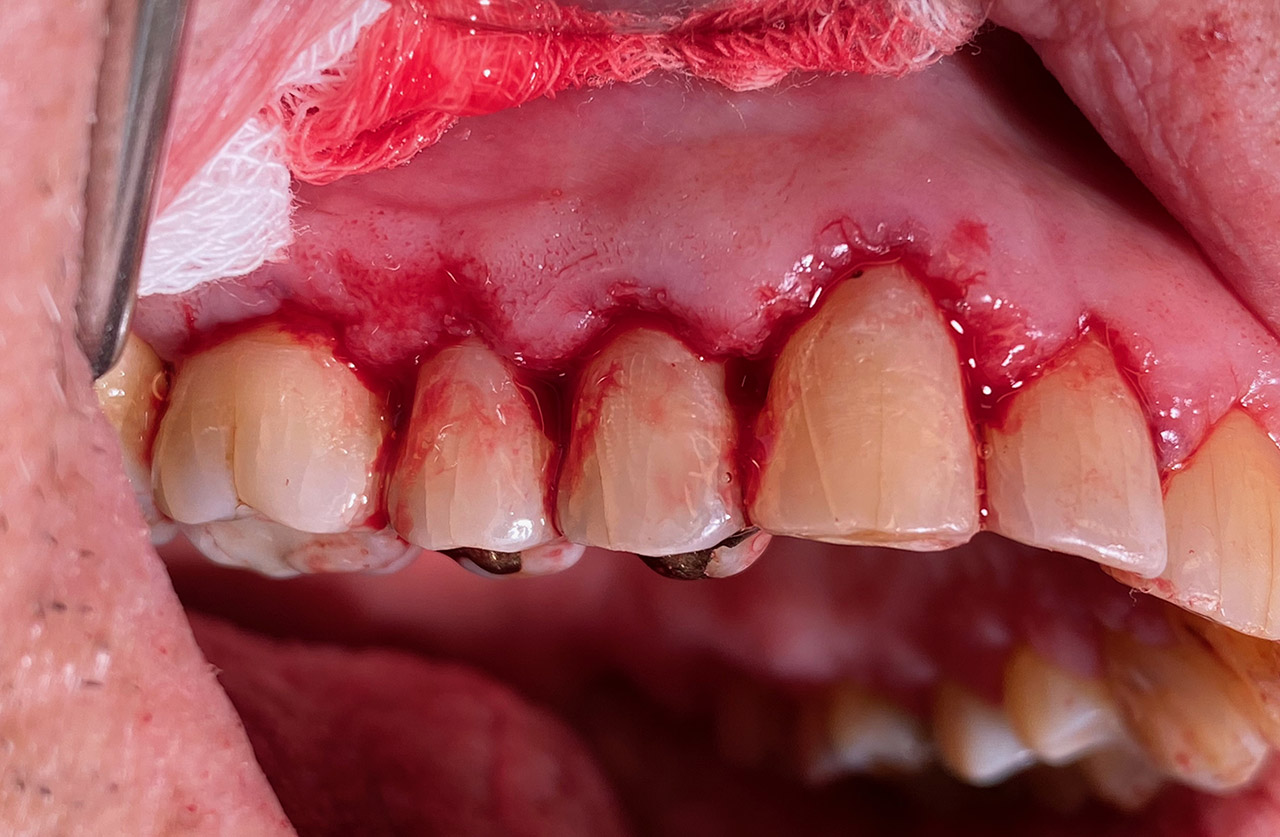

Parodontologie/Gingivahyperplasie:

Diagnose: Gingivahyperplasie durch Medikamente (Blutdrucksenker), unzureichende/nicht mehr mögliche Mundhygiene und überstehende Füllungen.

Therapie: Gingivektomie und anfinieren der Füllungen. Letztes Foto 1 Woche postOP.